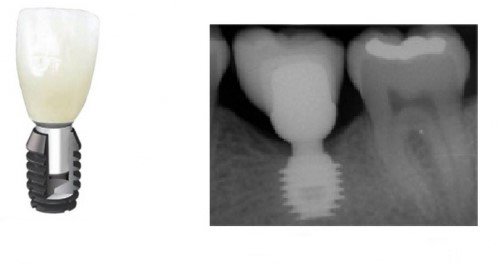

Когда мы говорим об ультракоротких (7 мм и менее) имплантах, то в первую очередь на ум приходит Bicon:

В далеком 1986 году американский профессор V. Morgan разработал концепцию субкрестальных коротких имплантов с фрикционной платформой. Последнее означает, что ортопедический интерфейс не имеет каких-либо антиротационных элементов (шестигранника и т. д.), а фиксация супраструктуры, коронки или абатмента, происходит путём «заклинивания»:

В этом есть, безусловно, революционность имплантов Bicon, их отличие от других современных имплантационных систем, в этом их главное преимущество и главный недостаток.